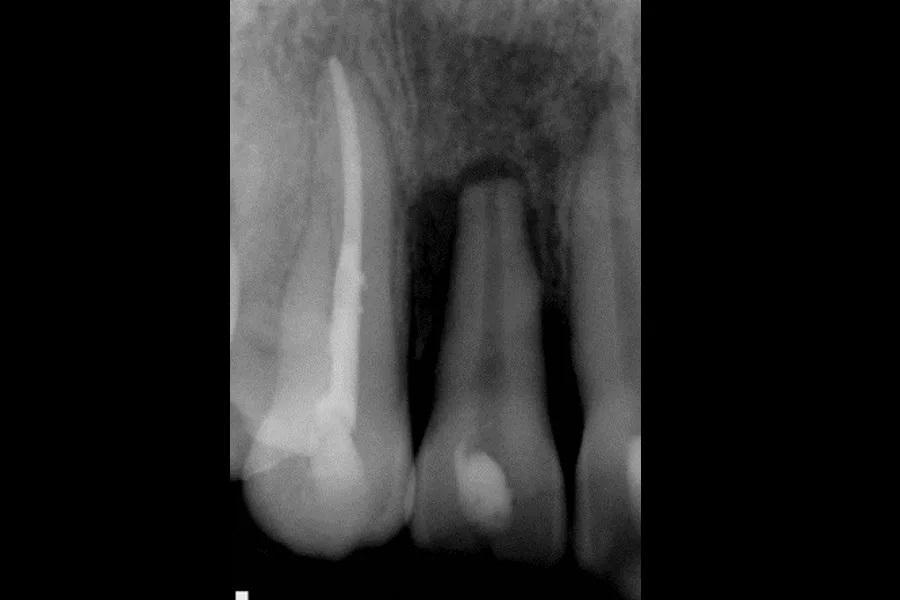

На следующее утро пациентка явилась в кабинет автора; с момента инцидента прошло 7–8 часов. Отмечались выраженные ушибы и множественные ссадины кожи лица и губ. Из-за явной подвижности зубов 1.2–2.1 была наложена шина на вестибулярной поверхности от 1.3 до 2.3 (Фото 1). Зуб 1.1 репозиционировали для лучшего выравнивания с 1.2 и 2.1. На периапикальных рентгенограммах выявлено смещение зубов 1.2 и 1.1 и, возможно, 2.1 и 2.2. Пациентке сообщили о необходимости эндодонтического лечения зубов 1.2 и 1.1; зубы 2.1 и 2.2 планировалось оценить на последующих контрольных визитах. В отделении неотложной помощи был назначен клиндамицин. На первичном стоматологическом приеме автор также назначил Medrol Dosepak (метилпреднизолон) для уменьшения отека и воспаления. Пациентке рекомендовали вернуться через 7–10 дней для оценки и эндодонтического лечения.

Фото 1. Рентгенограмма, сделанная на следующий день после травмы: наложена шина и выполнены первичные временные мероприятия.

На следующее утро пациентка явилась в кабинет автора; с момента инцидента прошло 7–8 часов. Отмечались выраженные ушибы и множественные ссадины кожи лица и губ. Из-за явной подвижности зубов 1.2–2.1 была наложена шина на вестибулярной поверхности от 1.3 до 2.3 (Фото 1). Зуб 1.1 репозиционировали для лучшего выравнивания с 1.2 и 2.1. На периапикальных рентгенограммах выявлено смещение зубов 1.2 и 1.1 и, возможно, 2.1 и 2.2. Пациентке сообщили о необходимости эндодонтического лечения зубов 1.2 и 1.1; зубы 2.1 и 2.2 планировалось оценить на последующих контрольных визитах. В отделении неотложной помощи был назначен клиндамицин. На первичном стоматологическом приеме автор также назначил Medrol Dosepak (метилпреднизолон) для уменьшения отека и воспаления. Пациентке рекомендовали вернуться через 7–10 дней для оценки и эндодонтического лечения.

Фото 1. Рентгенограмма, сделанная на следующий день после травмы: наложена шина и выполнены первичные временные мероприятия.